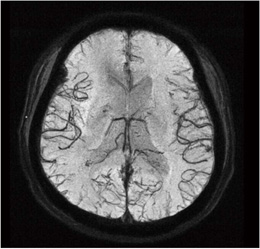

■Multi-Shot RSSG EPI(高分解能BOLD効果による高速撮像)

Multi-Shot RSSG EPIでは,磁化率効果による信号減衰だけでなく,磁化率の違う組織間のコントラストを強調した画像を得ることが可能です。高分解能なBOLD効果による静脈撮像として,脳静脈奇形や微小出血のスクリーニングへの応用が期待できる機能です。従来検討されているGRE撮像法ではなく,撮像時間が短いEPI撮像法を採用しました(図2)。

図2 Multi-Shot RSSG EPI MinIP画像